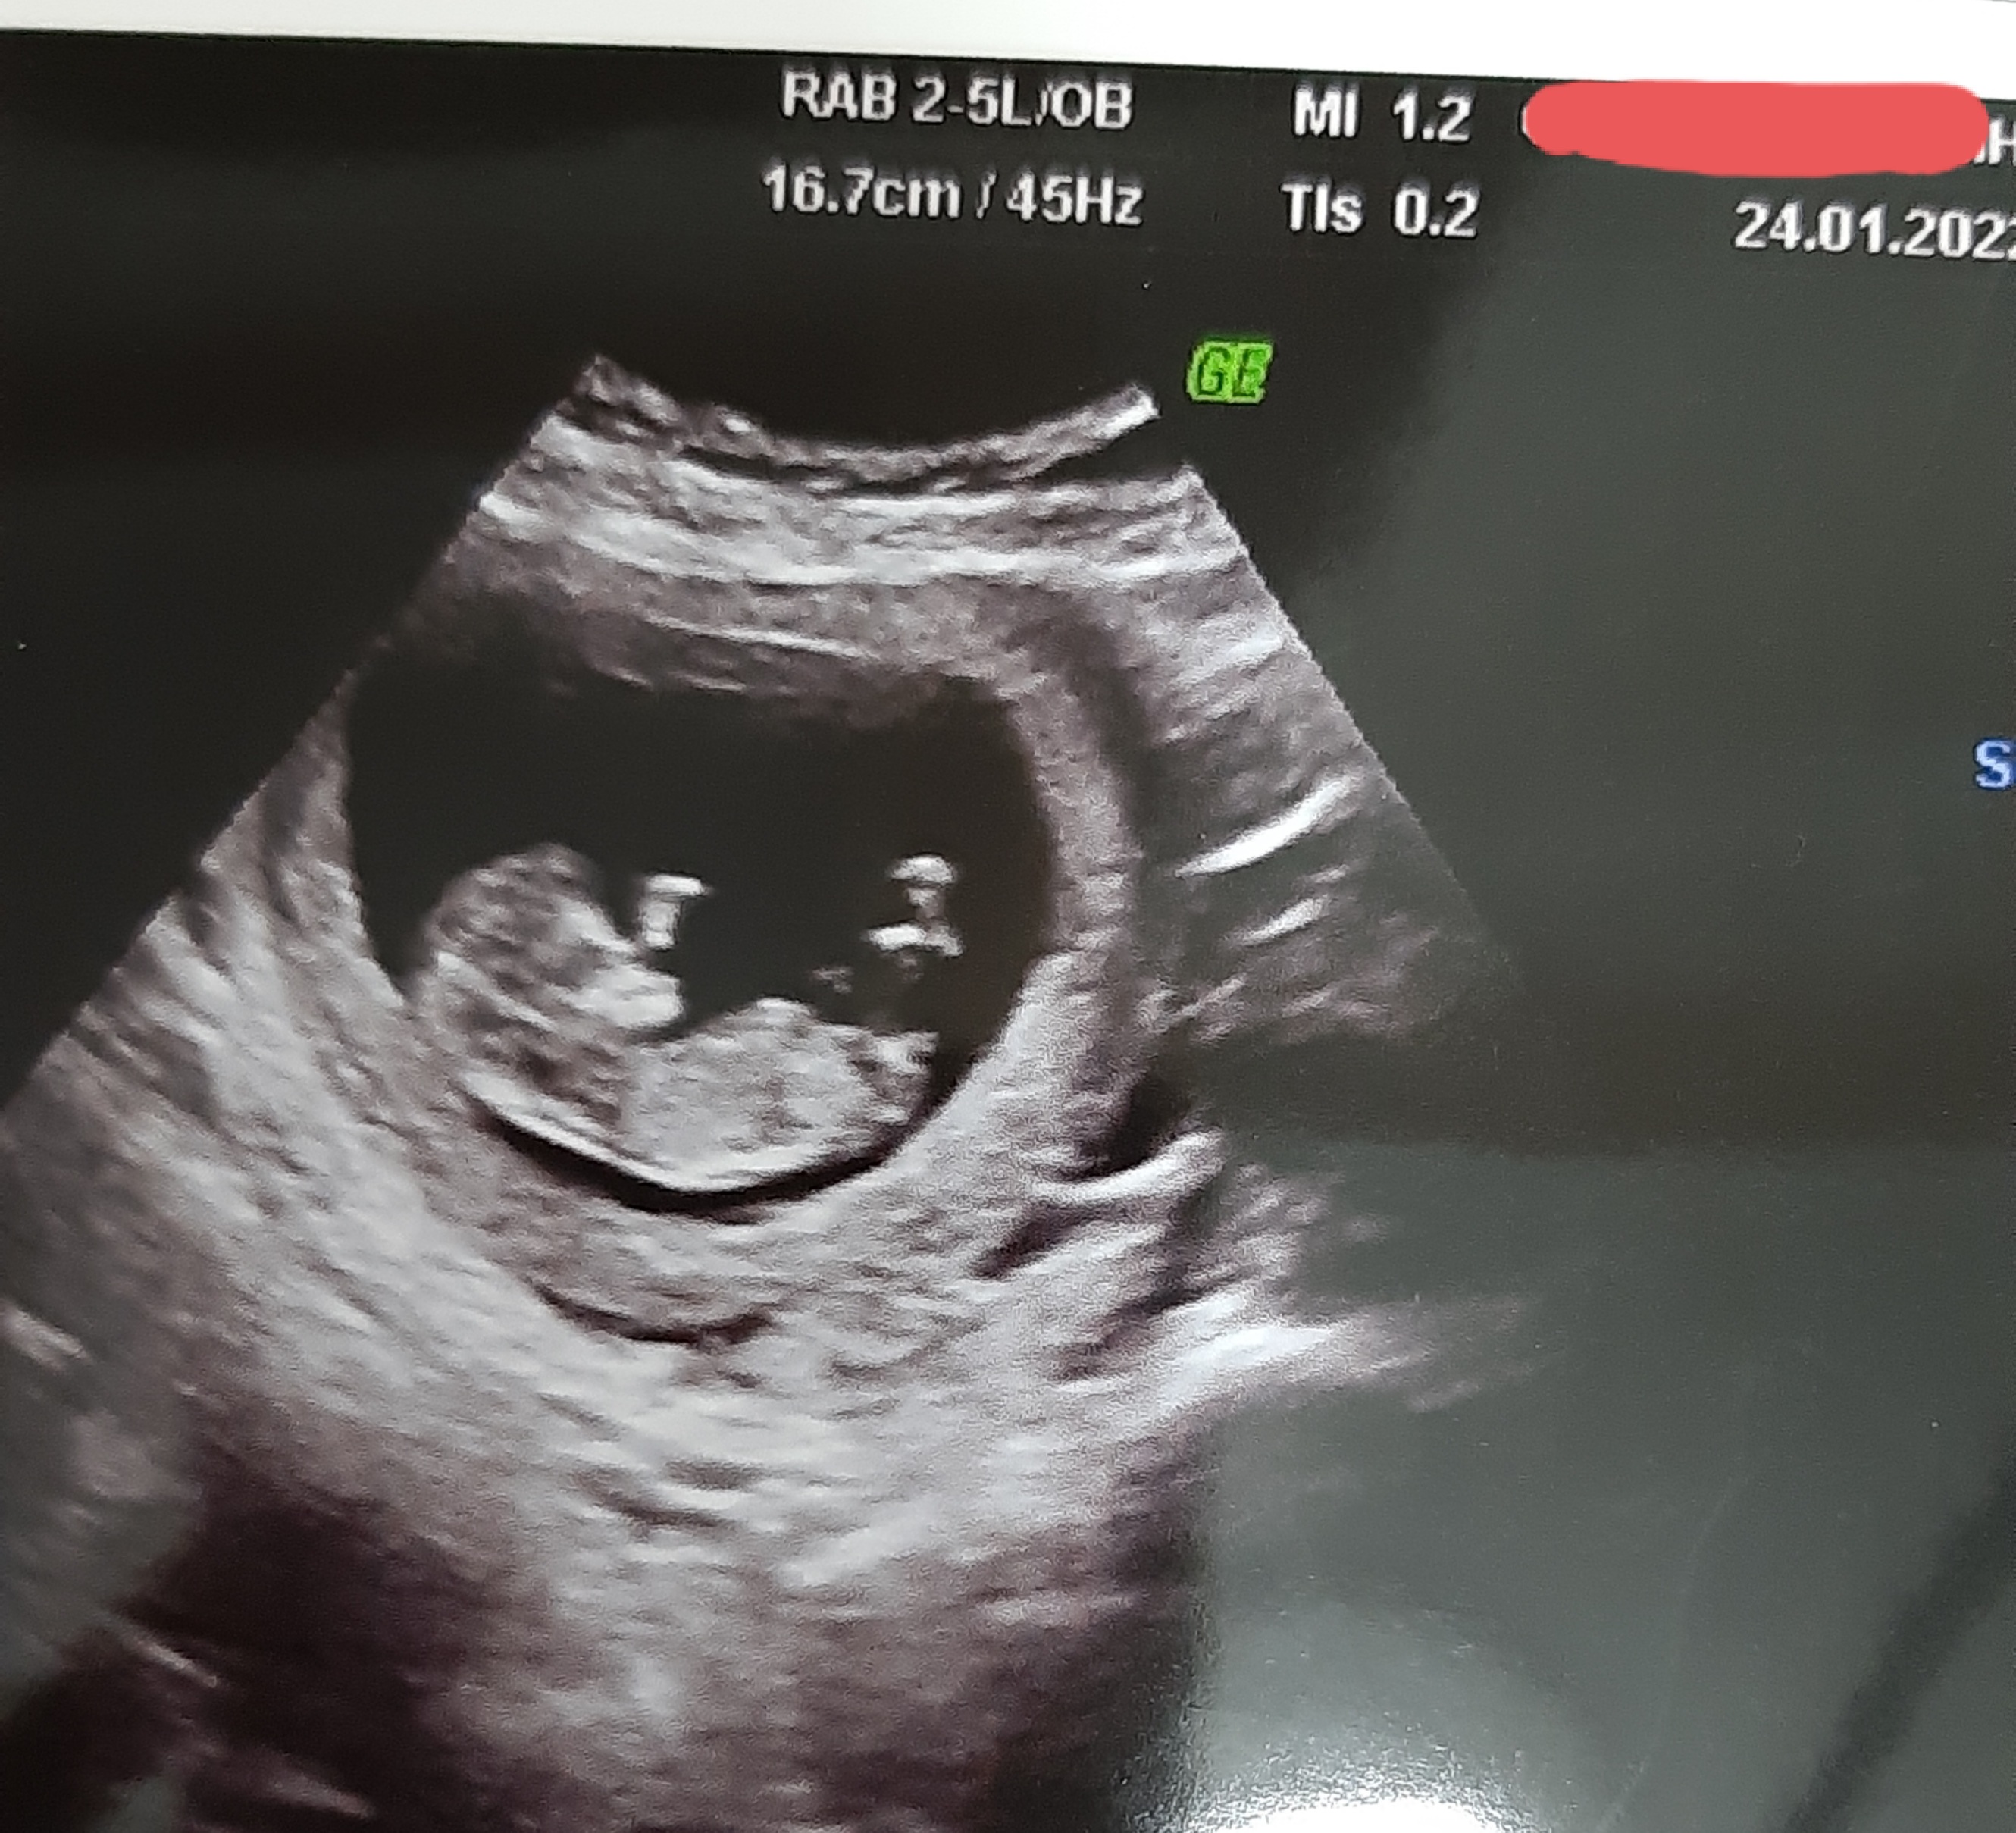

Kızlar Mrb sizce nub teorisine gire cinsiyet ne görünüyor

• 20220124_173446.jpg

1.2 MB · Görüntüleme: 535